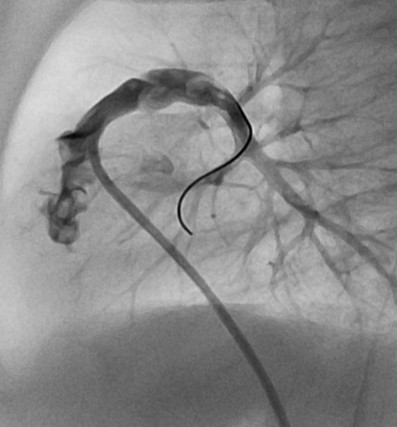

Panel A: LAO-cranial and B: 90° left lateral of the initial RV angiogram using the RCA catheter (by hand injection). While informative, the details of the outflow anatomy are best seen by a selective injection in the infundibulum.

Panel A: LAO-cranial and B: 90° left lateral of the selective injection into the infundibulum with the RCA catheter stabilized by a coronary wire in the RPA. Note the better anatomical definition for taking the measurements and identifying the potential landing zone.